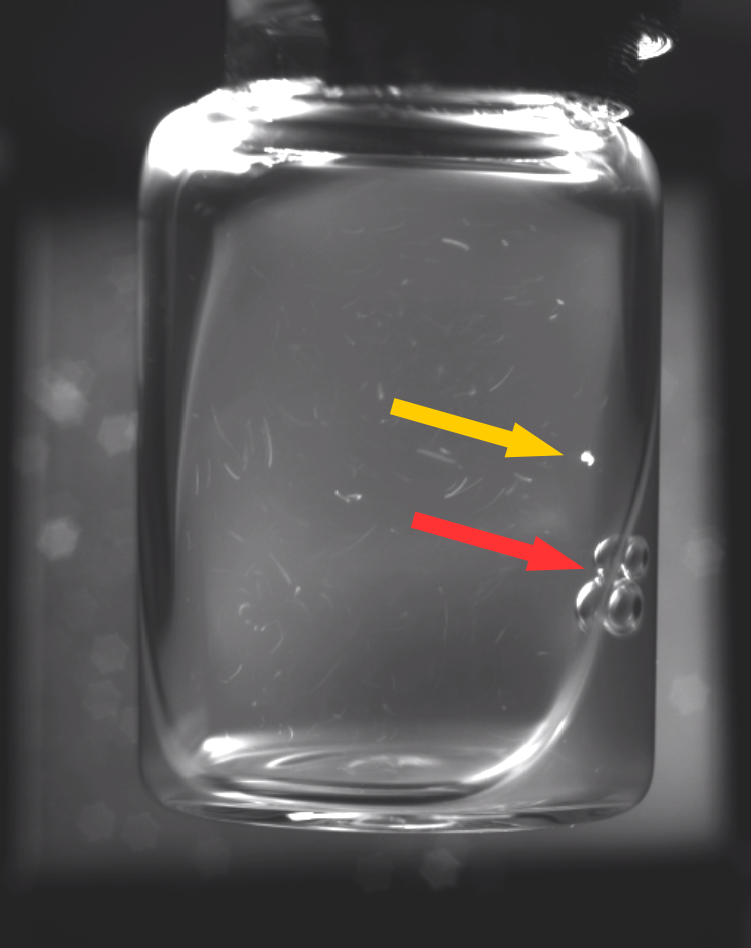

Correct lighting conditions are a prerequisite for identifying anomalies within liquid vaccines, since, due to a lack of contrast, their identification under natural lighting conditions is currently infeasible for human or automated visual inspection. A light intensity must be found that is sufficient for illuminating the vial while providing a moving contrast to identify the smallest particles [20]. To obtain a moving contrast human inspectors shake the vials to induce a swirl during manual inspections. Automated approaches meanwhile, such as the semi-automatic Seidenader V90+ inspection machine, use servo motors to stir up particles inside the vials. However, this approach has a side-effect of creating bubbles within the liquid. Furthermore, light reflections and dust particles resting on the outer surface of the vials can often be mistaken for anomalies within the liquid [20]. Opaque suspensions further increase the task difficulty by obscuring anomalies, which as a result are frequently only briefly visible. Figure 1 depicts some of these challenges.